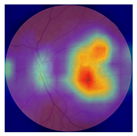

| No. | Fundus Image | Grad-CAM | Group | PRS | CNN | CNN+ML |

|---|---|---|---|---|---|---|

| 1 |  |  | Control | −2.13 | 0.63 | −0.34 |

| 2 |  |  | Control | −2.61 | 1.80 | −1.48 |

| 3 |  |  | AMD | 1.08 | 0.52 | −0.60 |

| 4 |  |  | AMD | −0.39 | −0.16 | −0.41 |